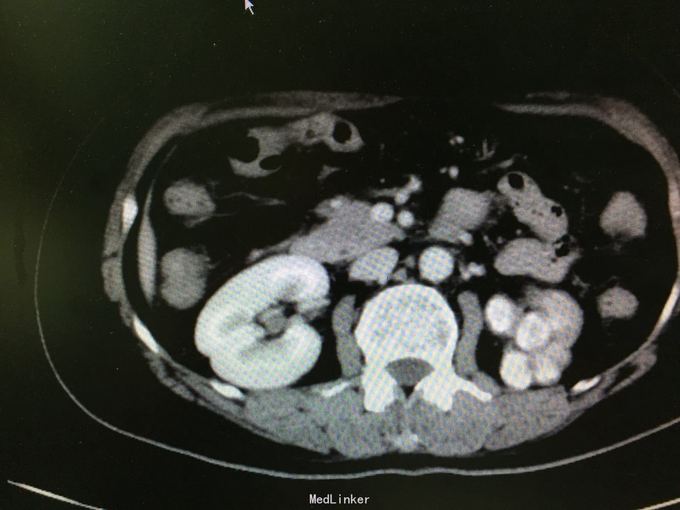

体检发现左肾萎缩11天 当地医院体检发现左肾萎缩,否认盗汗,发热。 2006年因盆腔结核住院治疗,自述规律抗结核治疗,具体不详。

查体:无殊,无阳性体征。 辅助检查:CTU:左肾萎缩,考虑肾结核自截肾。 胸部CT 右肺少量纤维化灶伴局部胸膜粘连改变。